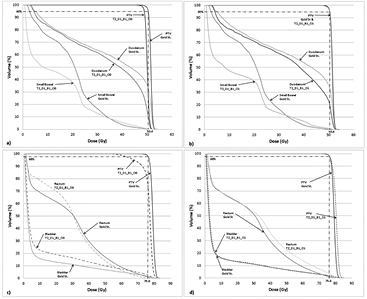

Standard image High-resolution imageInter-patient variation in pancreas and prostate cases

A total of five pancreas and prostate plans were used to study the variation in DVPs due to uniform rED assignment and a TMF. The variation in D95% for CT-based pancreas IMRT plans is at most −3.6% (table 8(b) panc2), even for plans with a TMF present. The variation in duodenum V45 and small bowel Dmean is at most −3.1% on CT-based plans. The differences for a larger number of DVPs and more OARs show that CT-based DVPs typically vary within −2% and −5.3% of the Gold St for uniform rED plans without and with a 1.5 T TMF present, respectively.

The interpatient variation in prostate D95% and D5% was within −3.8% of the Gold St for CT-based plans (table 9). The variation was found to be no more than −3.8% and −3.5% for D95% and D5%, respectively, on cases where dose recalculation was performed without a TMF present. When a 1.5 T TMF is present, the variations tend to be slightly larger and of magnitude −5.1% and −4.5% for D95% and D5%, respectively. Similar variations were observed for the bladder, rectum and femoral heads. When a TMF is not present during dose recalculation, the variations tend to be within 6% of the Gold St. However, the magnitude of variation was within 7% of the Gold St when a TMF is present during dose recalculation. The largest difference between rED plan and the Gold St was observed in the femoral head Dmax value in both situations.